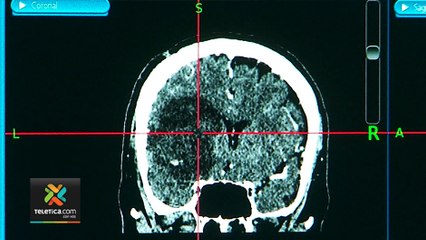

Tras más de 15 días de su infección, se dio a conocer que el menor, de quién no se conoce su identidad, falleció por la ameba comecerebros, que según autoridades, pudo contraer en un parque público br br